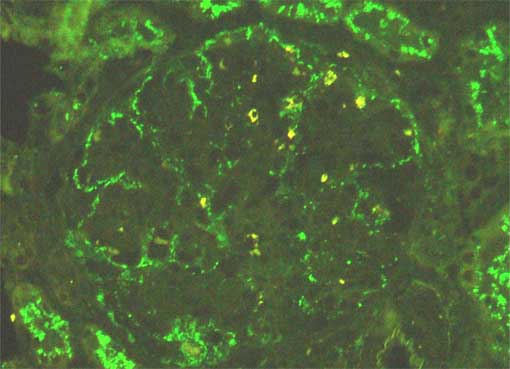

Figure 7.

Direct immunofluorescence using antiserum to IgG,

X400.